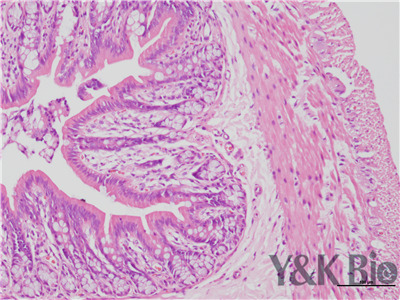

病理技术服务中HE染色法,学名苏木精-伊红染色,在法新疆石蜡切片技术里是经常用的染色法之一。石蜡切片常用于观察正常细胞组织的形态结构,是病理学用以研究、观察及判断细胞组织形态变化的主要方法。苏木精染液是碱性的 ,主要使细胞核内的染色质与胞质内的核糖体着紫蓝色 ;伊红为酸性的染料 ,主要使细胞质和细胞外基质中的成分着红色。HE染色法是组织学、胚胎、病理学教学与科研中基本、使用广泛的技术方法。

HE染色中要注意细胞核的分化程度,注意苏木素和伊红的效价,及时更换染液,一般实验周期为15个工作日。